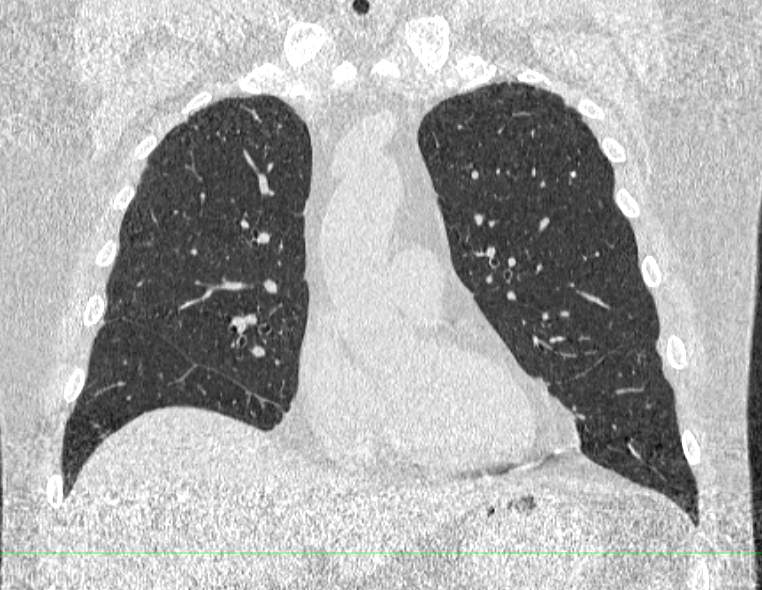

Мультиспиральная компьютерная томография – это современный высокоинформативный рентгенологический метод диагностики различной патологии легких. В условиях пандемии COVID-19 КТ легких стала основным методом диагностики для выявления даже незначительных изменений легочной ткани, вызванных любыми штаммами вируса.

Во время исследования рентгеновская трубка томографа вращается вокруг исследуемой области и производит множество послойных снимков с шагом 0,5-1 мм. Полученные снимки поперечного сечения с помощью компьютерной программы могут быть преобразованы в 3D-изображения исследуемого органа или участка ткани. Это позволяет выявлять практически все заболевания легких на ранних стадиях и назначать своевременное лечение.

В текущей эпидемиологической обстановке КТ легких является методом выбора при диагностике новой коронавирусной инфекции ( COVID-19).

С помощью КТ можно выявить новообразования на ранней стадии и туберкулез. Также КТ легких актуальна для наблюдения за послеоперационным и дооперационным состоянием проблемного органа.